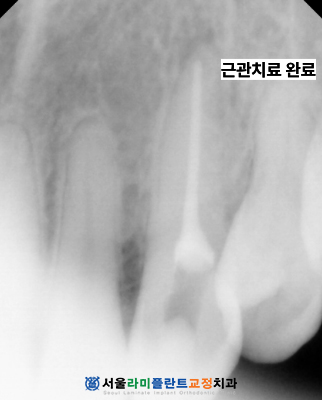

먼저 뿌리 끝에 발생한 염증을 제거하고

내부를 깨끗하게 소독하기 위해

총 세 차례에 걸쳐 정밀한

근관 치료를 시행하였습니다.

신경관 내부의 오염원을

완벽하게 제거하는 과정은

미백 결과의 안정성을 높이고

향후 재발을 방지하는 데

필수적인 단계입니다.